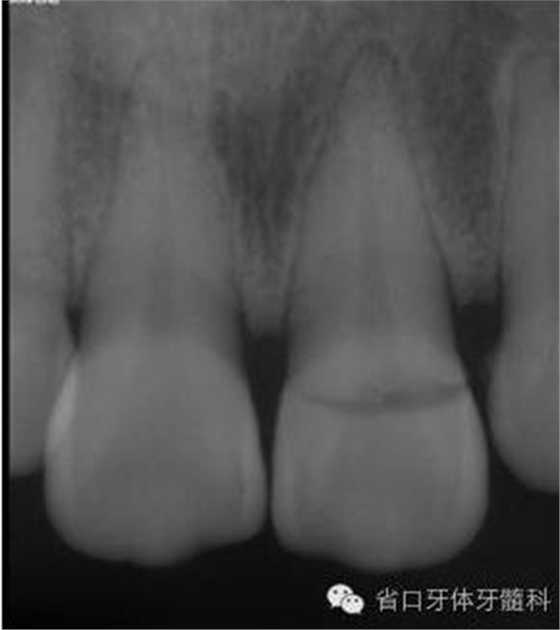

圖3. 術(shù)前X線片